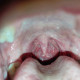

Izin dokter, pasien laki2 29thn dengan nyeri menelan 1 minggu. terdapat bercak putih pada area tenggorokan. pasien aktif merokok. Apakah sudah harus diberikan antibiotik?

Saya rasa perlu penangganan lebih lanjut ke dokter spesialis THT Untuk pasien ini  dengan nyeri menelan dan bercak putih di tenggorokan, terutama pada pasien aktif merokok, jadi ada beberapa  pertimbangkan kemungkinan diagnosisnya adalah :Diagnosis